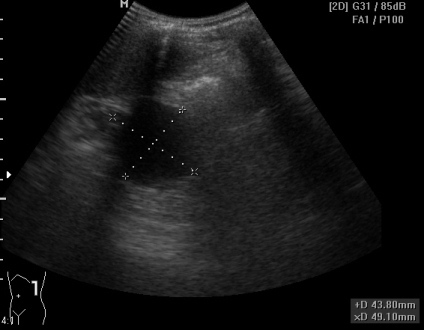

Женщина, 31 год, с умеренной болью в эпигастрии. Беспокоит боль периодически в течение 2 месяцев, усилилась примерно 2 недели назад. ОАК, ОАМ, БАК в норме, температура тела в норме. В малом тазу большое кол-во жидкости мелкодисперстной, особенно кпереди от матки (не сохранила ни скан, ни видео).

в проекции хвоста поджелудочной железы

Из того, что понятно: есть киста хвоста поджелудочной железы, жидкость в малом тазу (мелкодисперстная) и немного в брюшной полости (с нитями фибрина), кисты правого яичника.

1. По передней поверхности поджелудочной железы жидкость (1-ое видео и 3-ий сверху снимок) или мне кажется?

P.S.:Результат повторного кульдоцентеза: амилаза 817, эритроциты в большом количестве.

Из представленных Вами материалов. Пересматриваю раз за разом первый клип - отек парапанкреатической ткани. Исключайте о.панкреатит.

Геморрагическая жидкость характерна для о.панкреатита.